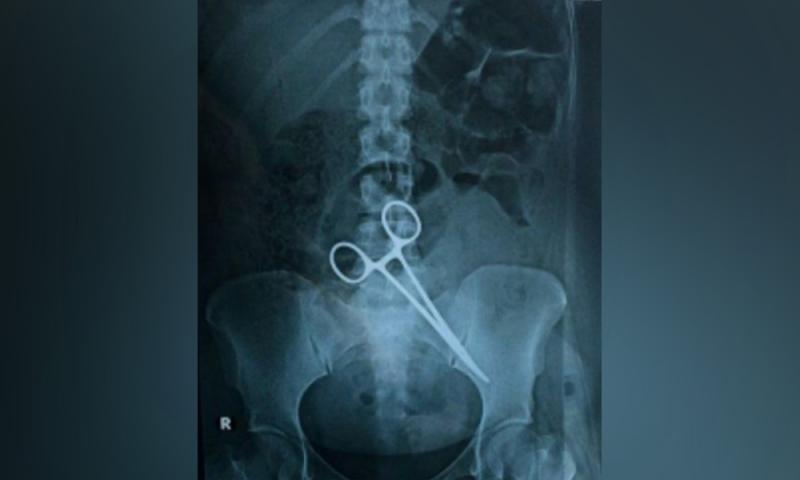

A 25-year-old woman who underwent a Caesarean procedure began feeling intense pain in her abdomen two days after she was released from a Kuala Lumpur hospital.

She was told it was normal after such a procedure but the pain in her left abdomen intensified when moving or changing body positions, causing her to vomit frequently...